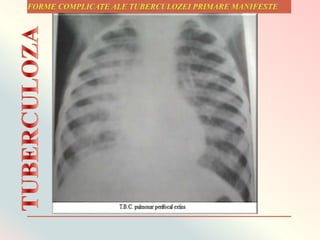

Complexul primar poate evolua cu complicaţii precum:

 compresia gangliono-

bronşică;

 atelectazii;

 fistulă ganglio-

 cavernă

ganglionară.

 procese inflamatorii

extensive benigne care

se numesc

epituberculoze;

TUBERCULOZA